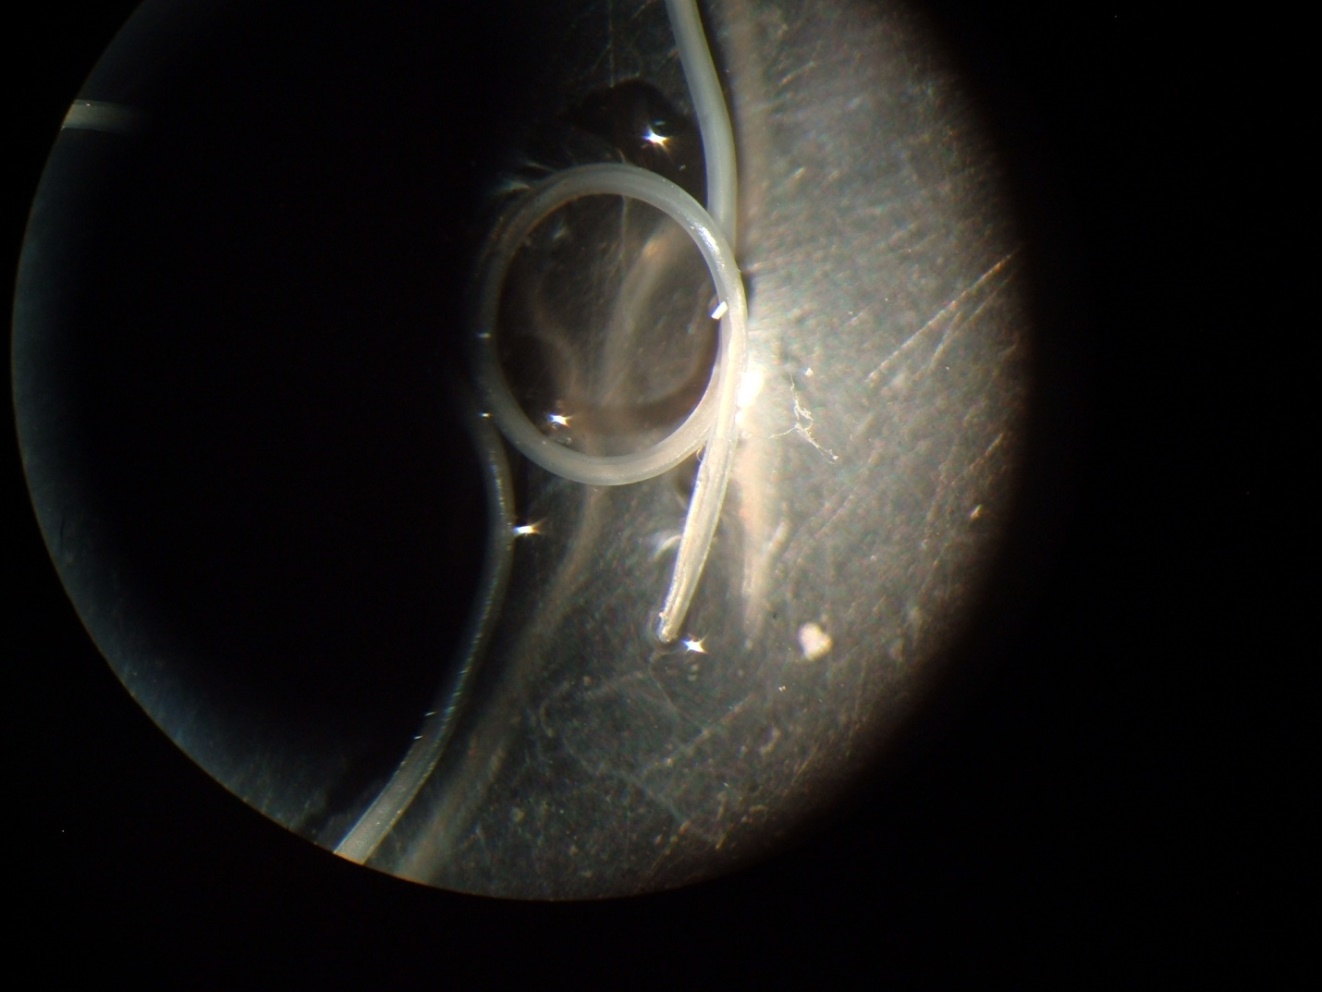

At admission, the complete blood cell count was normal, without eosinophilia. The nodule was surgically removed under local anesthesia, with a surprinsing inside outcome: a living and coiled roundworm emerged intact from lesion. The worm was sent to Colentina Hospital-Parasitic Diseases Department for identification and the patient for medical assessment. Nematod was introduced in a 70% ethylen alcool solution with 5% glycerin, being macro and microscopically examined (Figure 2).

Figure 2 Clinical case: the intact imature worm.

The worm

The worm was  white, thin and round, measuring about 10.5 cm in length and 0.5 mm in its maximum diameter. The both ends were slender. Microscopically, the anterior extremity was blunty rounded and larger than the posterior one (Figure 3). The thick  cuticule-outer layer of filaria worm showed well-definite longitudinal ridges with fine transversal striations. The genital pore was identified at aproximately 1 cm from the anterior end. These features have suggested  the presence of an immature female of Dirofilaria repens Railliet & Henry, 1911 (subgenus Nochtiella).